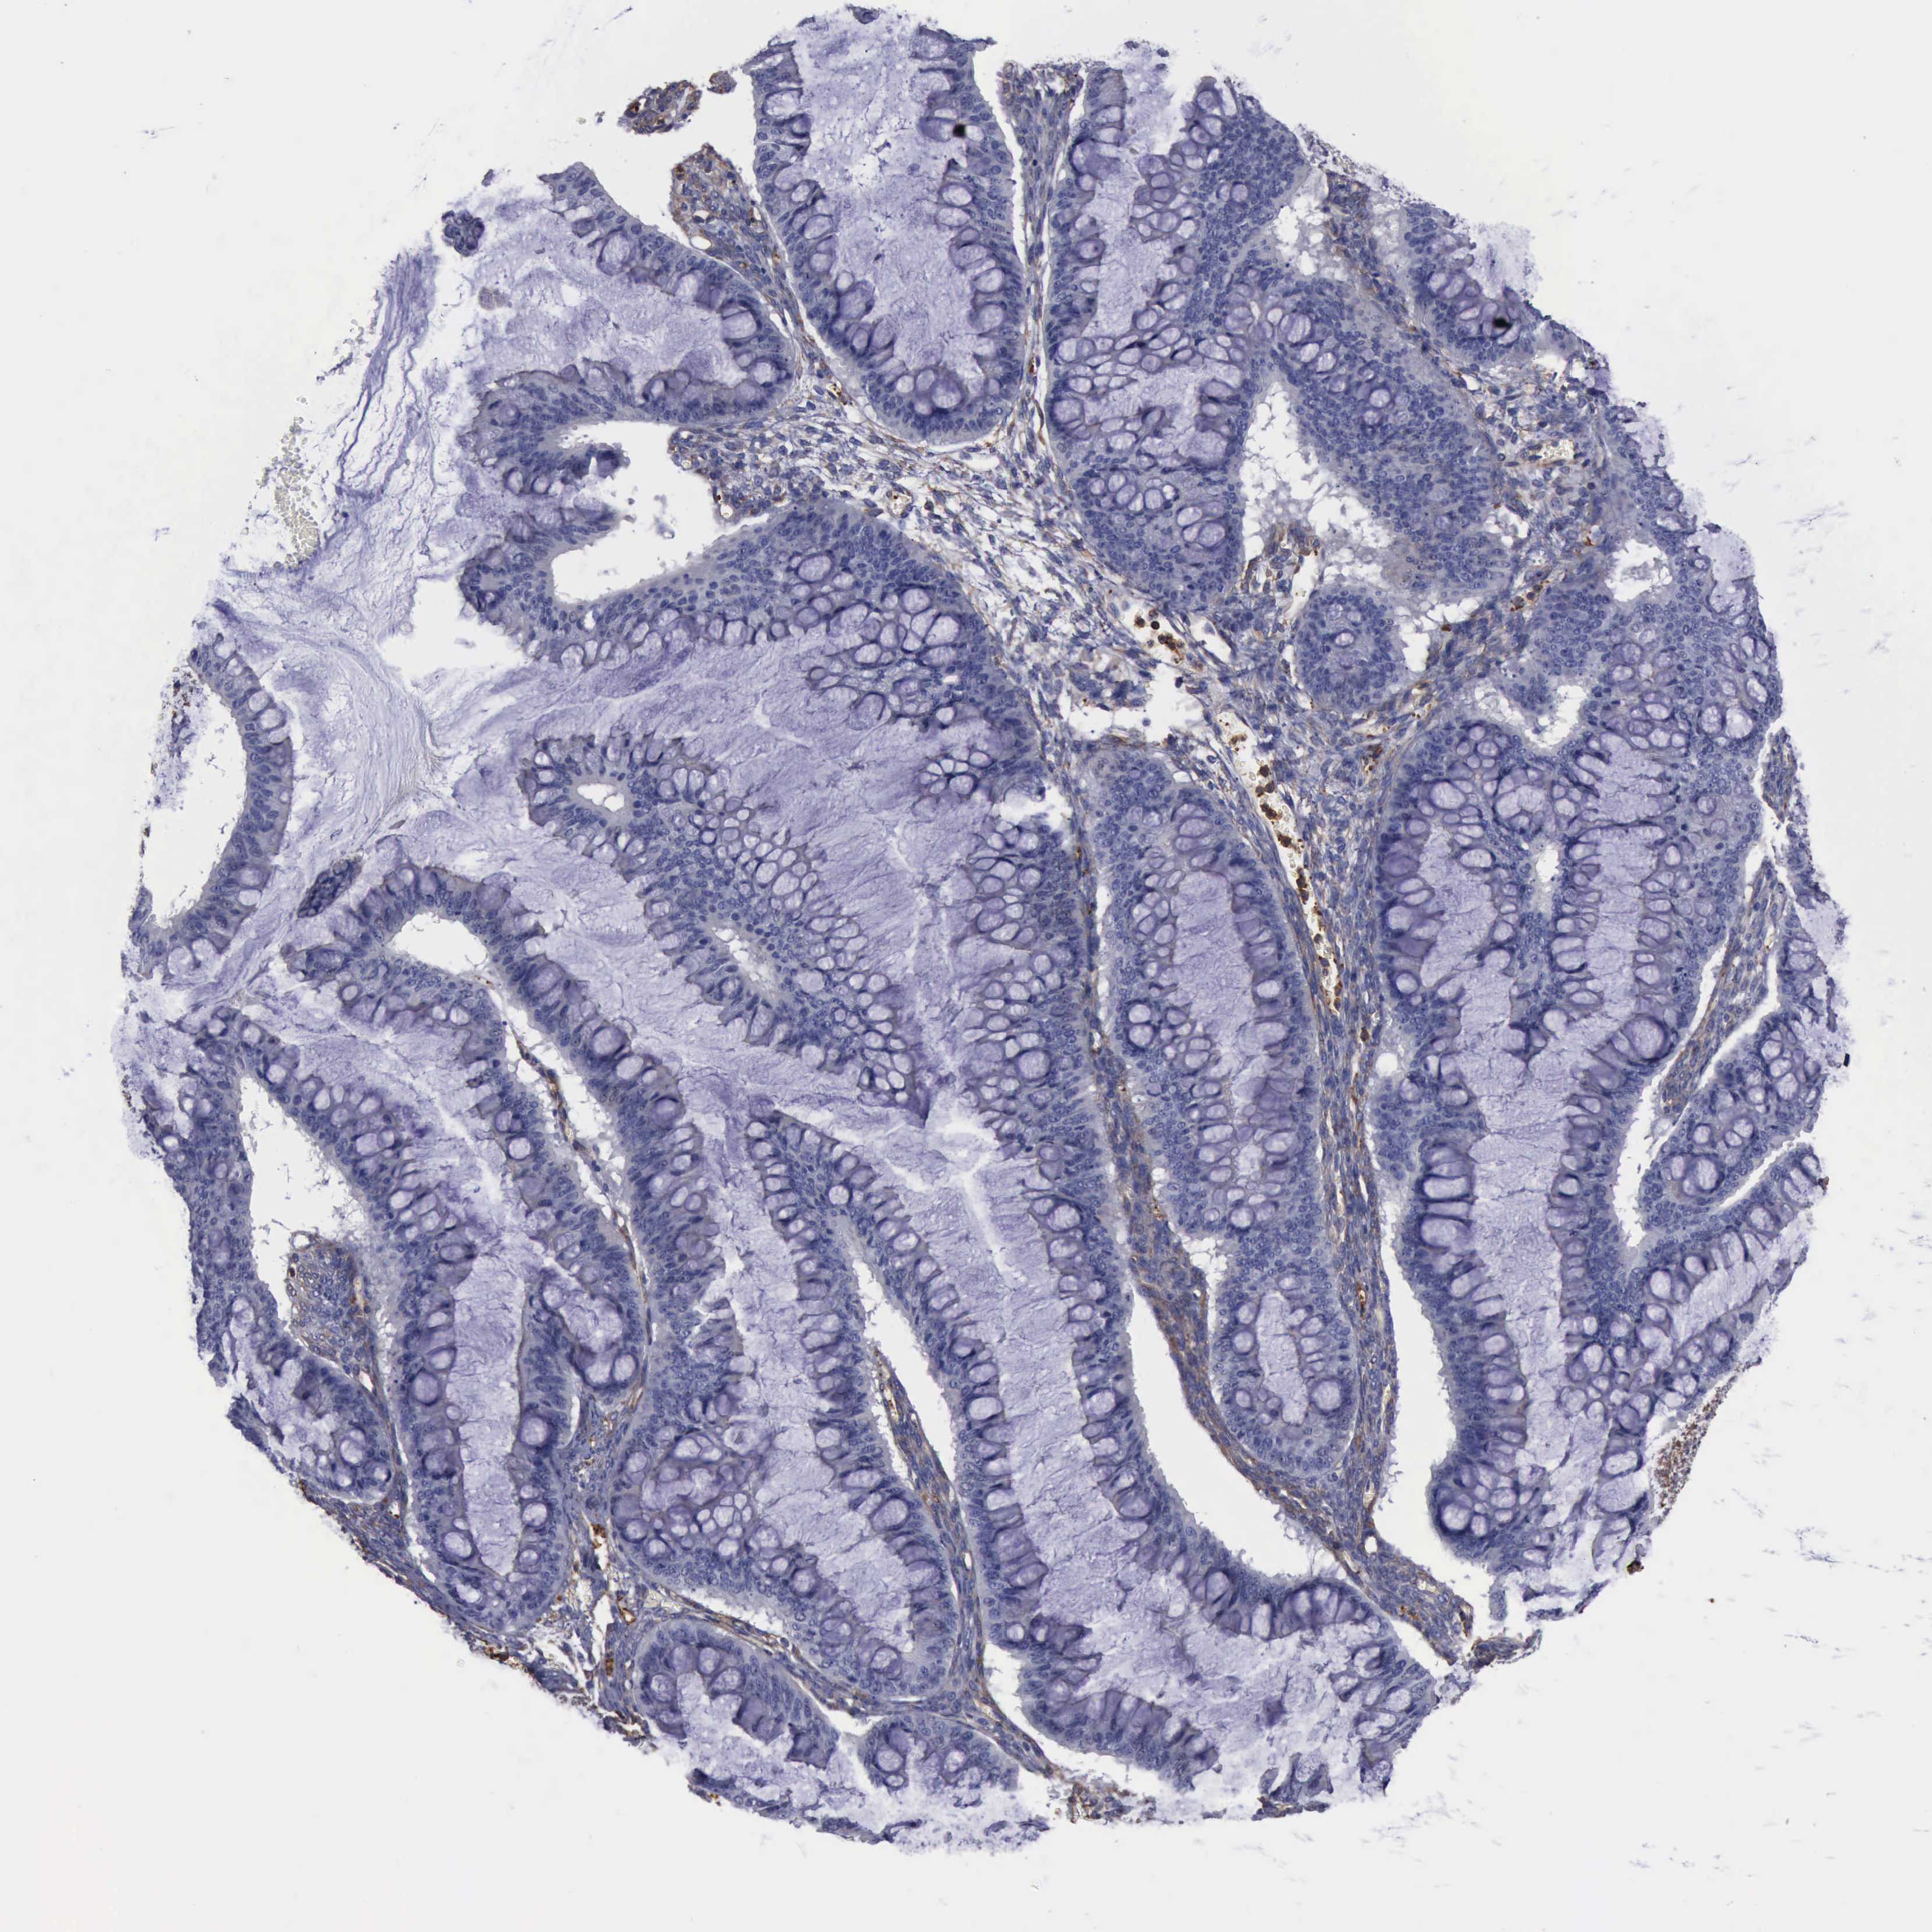

OVARIAN CANCER - Protein expressioni

A mouse-over function shows sample information and annotation data. Click on an image to view it in a full screen mode. Samples can be filtered based on level of antibody staining by selecting one or several of the following categories: high, medium, low and not detected. The assay and annotation is described here.

Note that samples used for immunohistochemistry by the Human Protein Atlas do not correspond to samples in the TCGA dataset.

Antibody stainingi

Antibody staining in the annotated cell types in the current human tissue is reported as not detected, low, medium, or high, based on conventional immunohistochemistry profiling in selected tissues. This score is based on the combination of the staining intensity and fraction of stained cells.

Each image is clickable and will lead to virtual microscopy that enables deeper exploration of all samples and also displays staining intensity scores, fraction scores and subcellular localization as well as patient and tissue information for each sample.

Antibody HPA001115

Antibody HPA002925

Antibody CAB000356

Staining

High

Medium

Low

Not detected

Cystadenocarcinoma, mucinous, NOS

Carcinoma, endometroid

Cystadenocarcinoma, serous, NOS